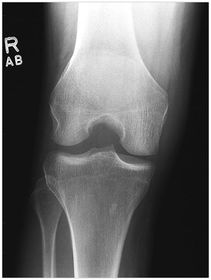

A. base of patella B. apex of patella C. tibial tuberosity D. neck of fibula E. head of fibula F. apex of head of fibula G. superimposed lateral and medial condyles H. patellar surface